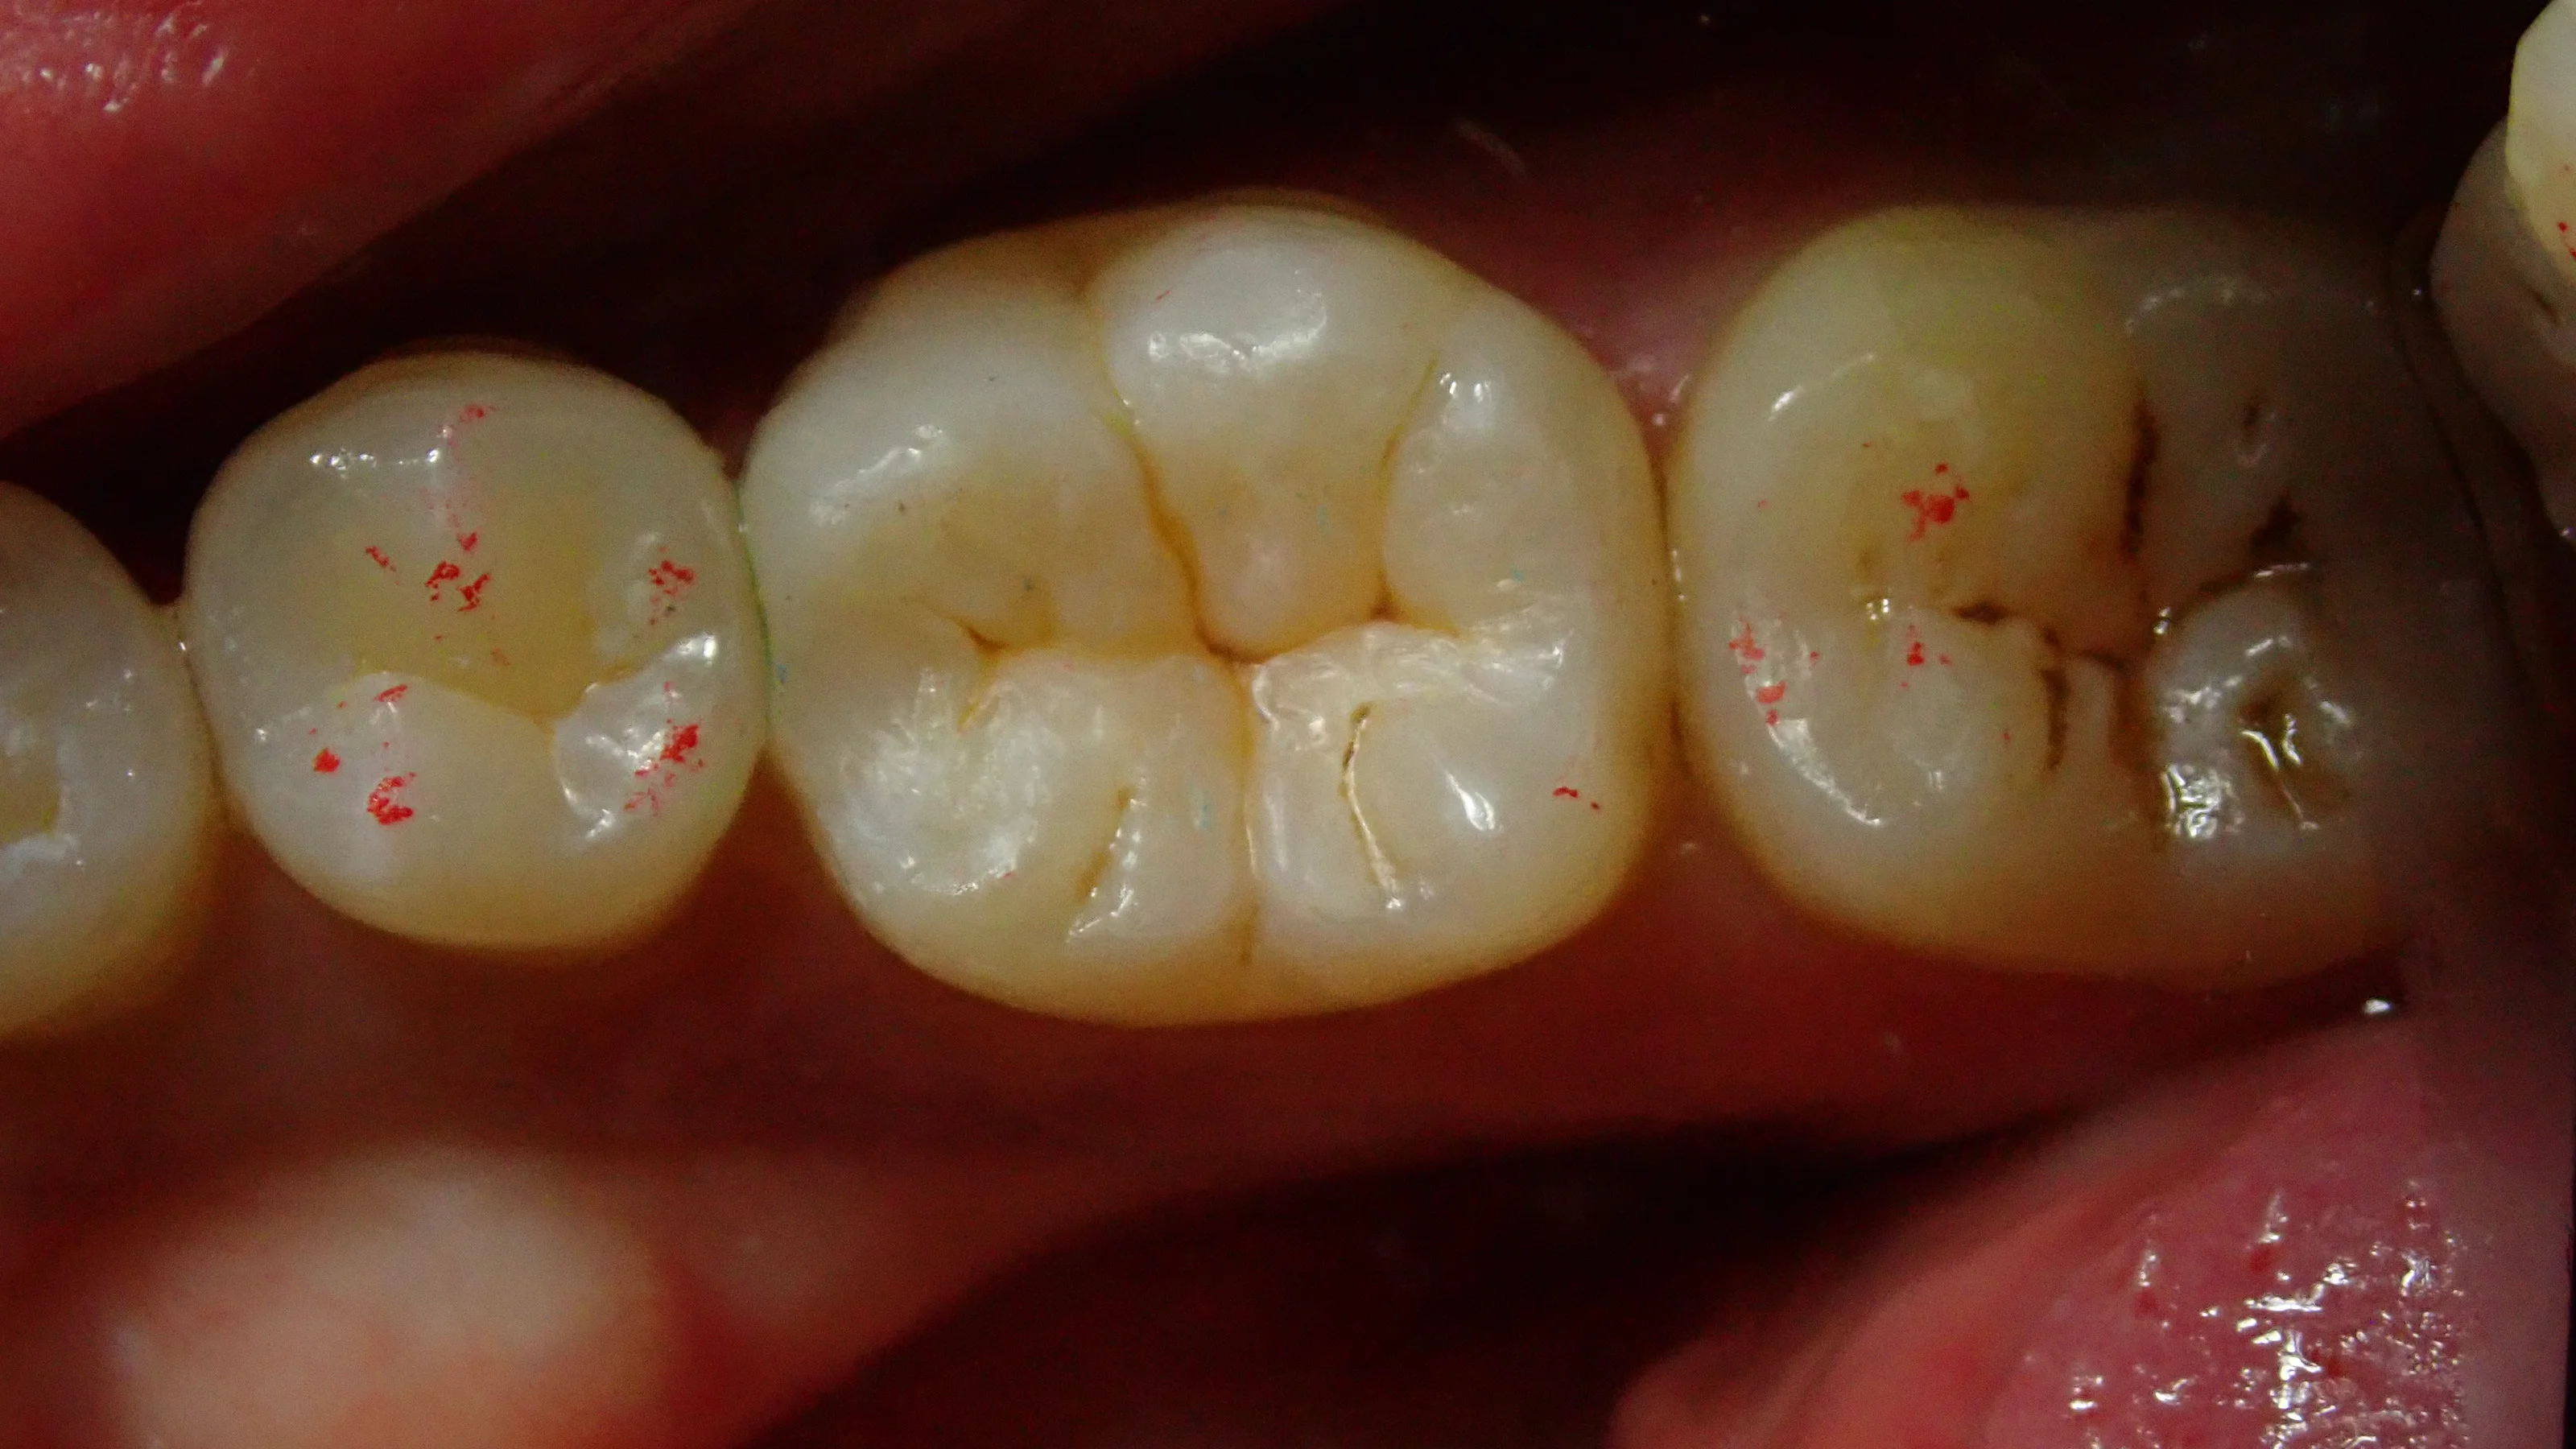

まずは術前の写真です。

どうやら保険適用内のCR(コンポジットレジン)で治療を受けられたようですが、割れてしまい、そこから中に虫歯が侵入してしまったようですね。